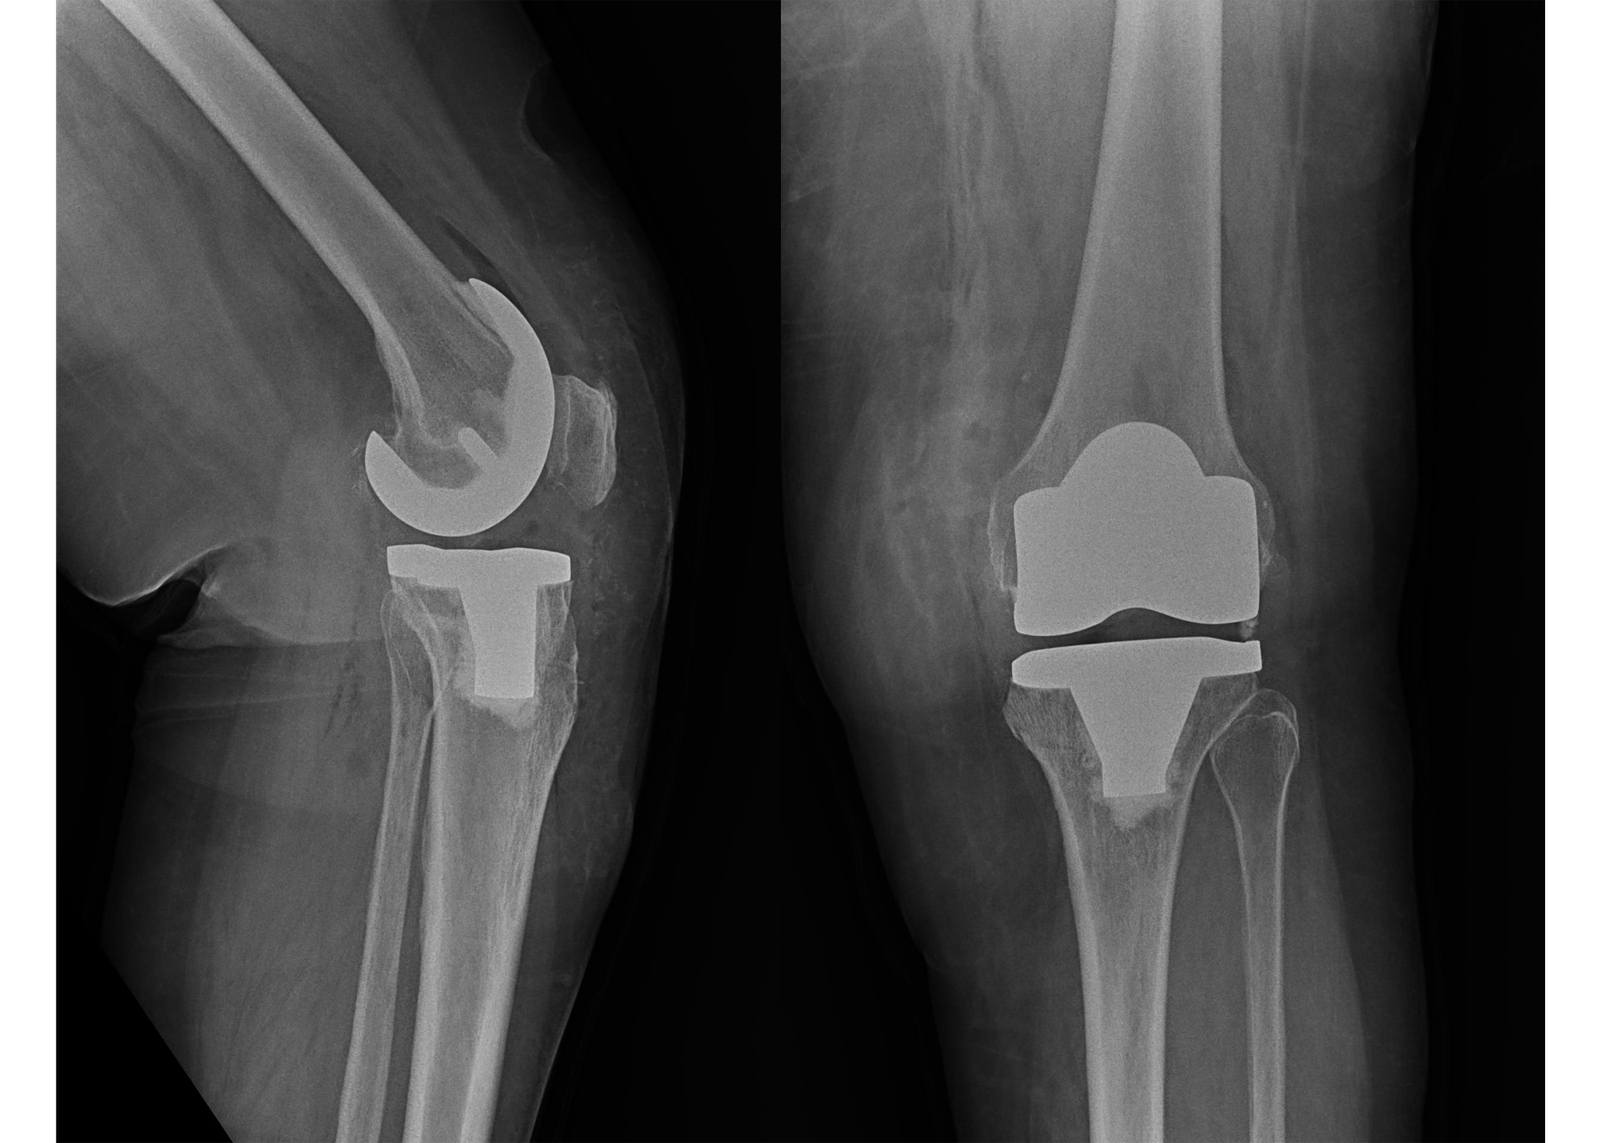

1. Total Knee Replacement (TKR):

Our Total Knee Replacement procedures are designed to relieve pain and restore function in patients suffering from severe arthritis or knee damage. Using advanced surgical techniques and high-quality prosthetic implants, we ensure that patients receive the best possible care and achieve optimal recovery.

X-Rays